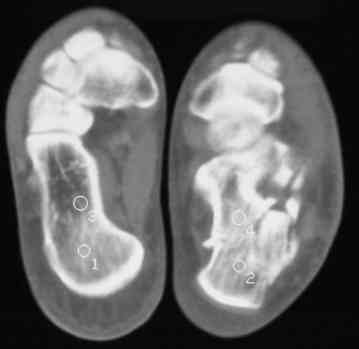

Уважаемые коллеги! Пришел на консультацию больной - "растяжение связок левого голеностопного сустава" полтора месяца назад, поскольку был в морях, на ногу не наступал. Снимки и КТ - в приложении.

Как бы кто лечил с учетом времени после травмы - 52 дня? Человек физического труда. Социальные запросы самого больного высокие, плюс медкомиссии перед рейсами - с хромотой нельзя!

Целесообразно Вашему пациенту выполнить подтаранный компрессионный расклинивающий артродез с использованием канюлированных винтов.

52 дня - неудобный срок, особенно учитывая недостаточную нагрузку ноги в плавании. Я обычно пациентам в такой ситуации назначаю препараты кальция и дозированную нагрузку, через 1-1,5 месяца после - оперируем. Операция показана для восстановления оси и высоты пяточной кости, устранения грушевидного расширения ее и вальгусного отклонения,устранения болевого и посттромботического синдромов. Тему лечения осложненных переломов пяточной кости в поздние сроки не освещал в известной Вам монографии сознательно: это одна из глав диссертации моего ученика С.М.Платонова.